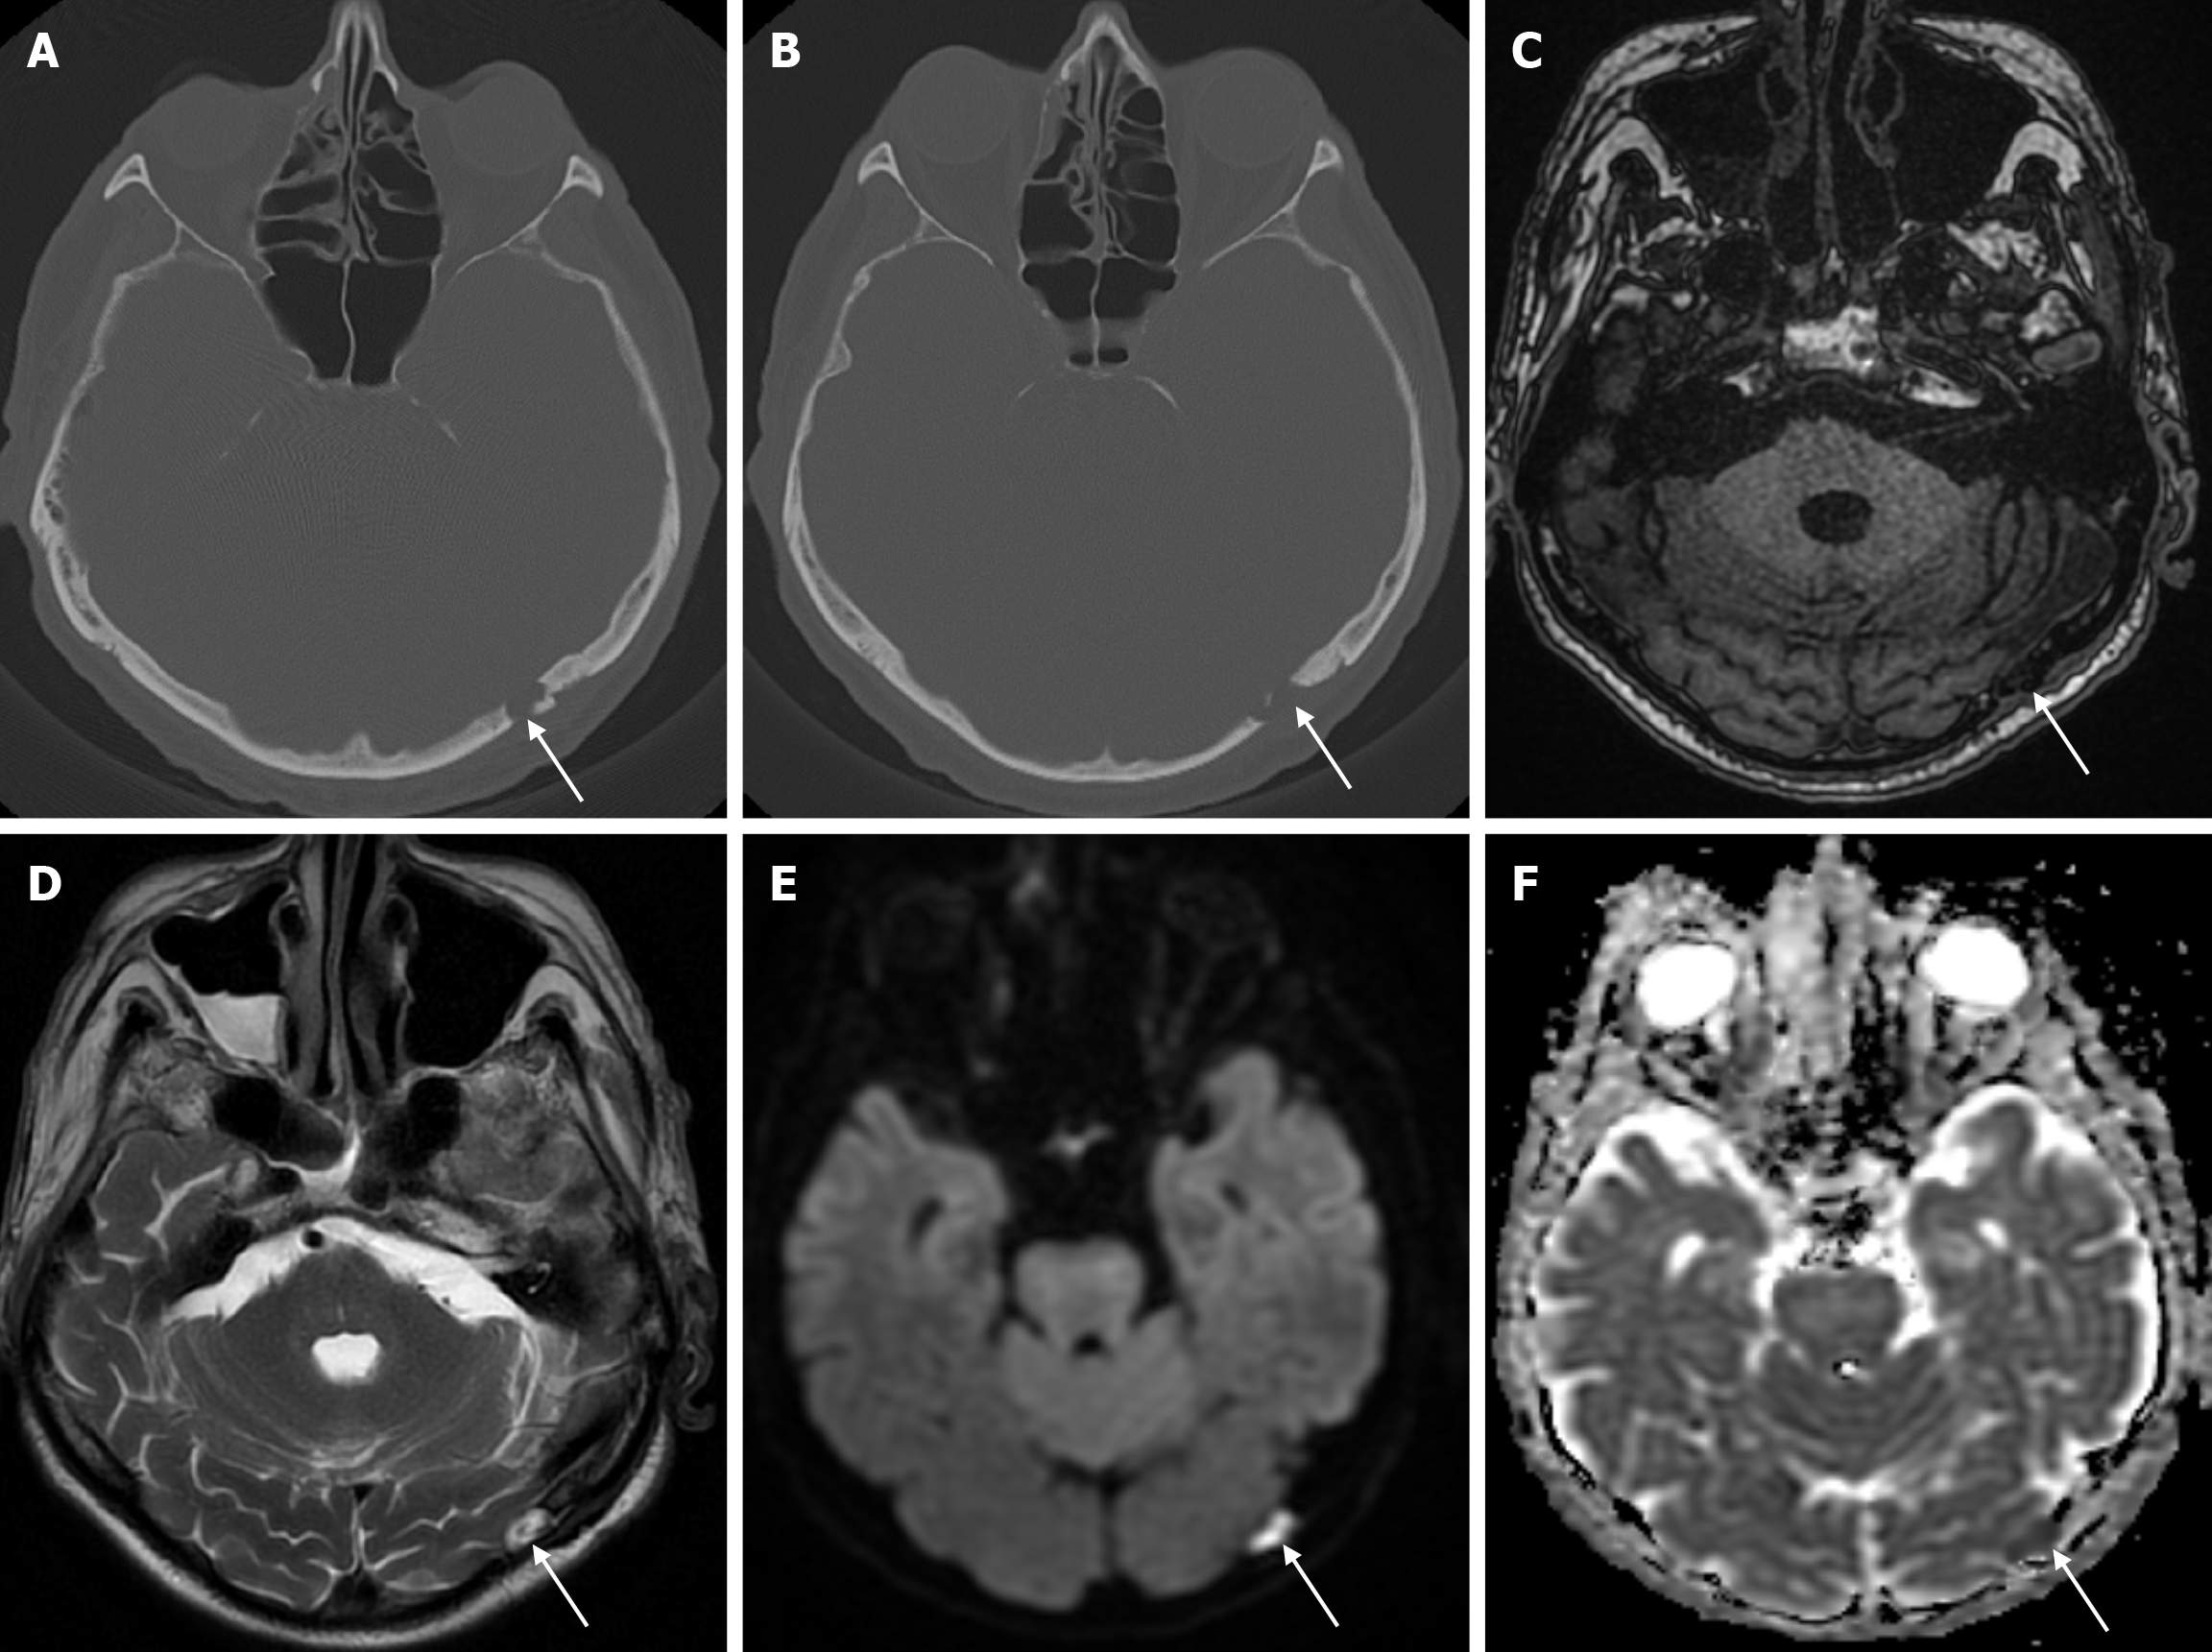

The transcalvarial venous channels are the openings in the calvarium that connect the dural venous sinuses to the extracranial veins via emissary veins. They are usually seen as serpentine or linear lucencies with sclerotic margins along the skull, and when these vessels are dilated they are known as venous lakes. Venous lakes are sometimes confused with fractures or sutures[14]. Venous lakes are present in about 15% of patients and are not associated with age or gender[15]. Venous lakes appear on CT as round or oval lucencies at the level of the skull base (Figure 3). On MRI, they show medium or low signal intensity on T1-weighted images, high signal on T2-weighted images, and significant contrast enhancement is seen in contrast-enhanced series[14]. It is important to distinguish venous structures from metastases. Metastases often show restricted diffusion within the lesion due to high cellularity. In addition, metastases may show increased blood flow within the lesion. Metastases often invade adjacent tissues[15].

Epidermoid cysts are small or medium-sized, benign, and slow-growing tumors that arise from the remnants of ectodermal cells in the bones of the skull. These cysts can also develop after trauma or surgery. Epidermoid cysts are lined with squamous epithelium. They contain deposits of cholesterol and keratin. These cysts constitute less than 1% of primary intracranial tumours, while intradiploic epidermoid cysts account for less than 0.25% of intracranial tumours. These tumors can occur at any age from the first decade of life to the seventh decade, with a mean age of 32-38 years, and there is no gender predilection. Epidermoid cysts are most commonly found in the frontal, parietal and occipital regions and often involve more than one bone. Epidermoid cysts appear on plain radiography as round or lobulated lytic areas with smooth and sclerotic margins. On CT they appear as non-contrast enhanced intradiploic lytic hypodense lesions with smooth sclerotic borders. Epidermoid cysts often cause remodeling and widening of the inner and outer tables. Epidermoid cysts that appear hyperdense on CT due to bleeding, calcification or high protein content are called white epidermoids and are observed quite rarely. On MRI, epidermoid cysts appear isointense/hyperintense on T2-weighted and fluid-attenuated inversion recovery (FLAIR) images and slightly hyperintense on T1-weighted images (Figure 4). These lesions restrict diffusion on diffusion-weighted imaging but show no contrast enhancement on contrast enhanced sequences[19].

Leptomeningeal cysts can develop as a rare complication of linear skull fractures in children. The incidence is reported in the literature to be between 0.05% and 0.1%. They are usually seen in children under the age of 3. These cysts most commonly occur in the cranial convexity but can also be seen in the posterior fossa and orbital roof. This complication develops as a result of dural tear associated with skull fracture. Laceration of the dura mater leads to herniation of the leptomeninges and filling with CSF. The continuous pulsatile pressure of the CSF and the expansion of the cyst cause resorption of the adjacent bone, erosion of the bone edges and expansion of the skull fracture. The fracture site, together with the thickness of the soft tissues, can be seen on plain radiography. While bone fractures can be better demonstrated with CT imaging, MRI is more useful in distinguishing leptomeningeal cysts from other pathologies. Leptomeningeal cysts are isointense with cerebrospinal fluid on both T1-weighted and T2-weighted images (Figure 10). Associated pathologies such as subdural fluid collections, hematomas, encephalomalacia, and ventricular dilatation may also be seen on CT imaging and MRI. Early diagnosis is important because of the risk of neurological deterioration and seizures, and treatment includes dural repair and cranioplasty[35].